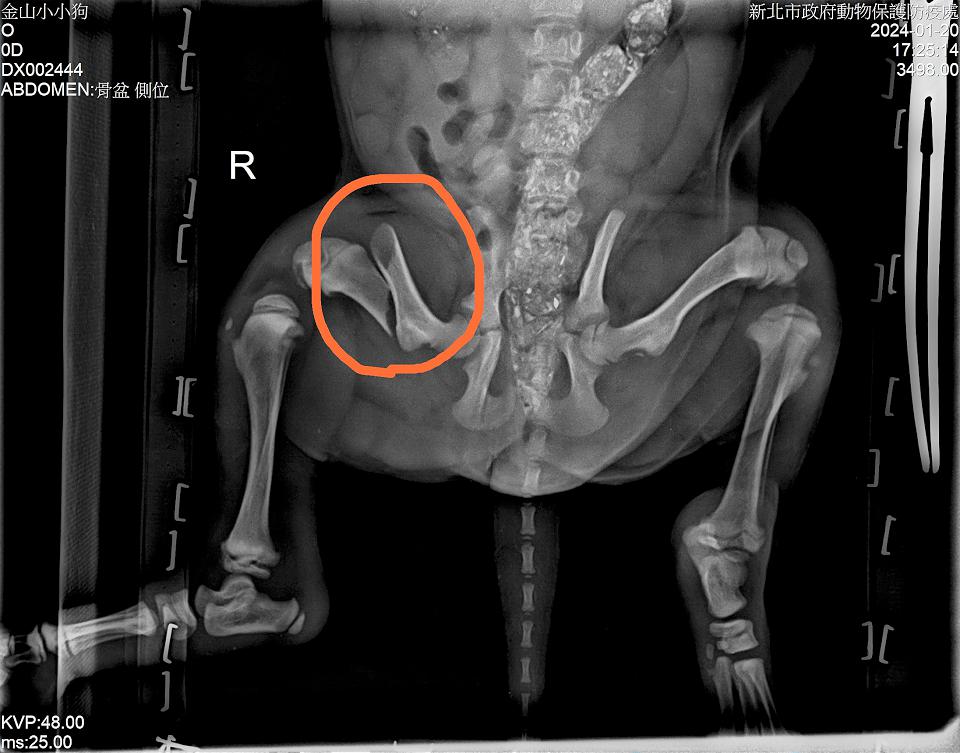

動保處獸醫師李建沛表示,小黑犬大腿骨斷端錯位嚴重,尾巴根部有大面積擦傷,且年齡不到2個月,若不即時進行外科手術,一旦骨頭斷端處形成結締組織,血管、肌肉及軟骨區域錯位生長,會增加手術困難度及影響骨頭復原程度,幸好即時送醫手術治療,再加上術後復健良好,才能免除跛腳的危險。

小黑狗大腿骨折嚴重,幸及時開刀後恢復健康。翻攝新北市政府